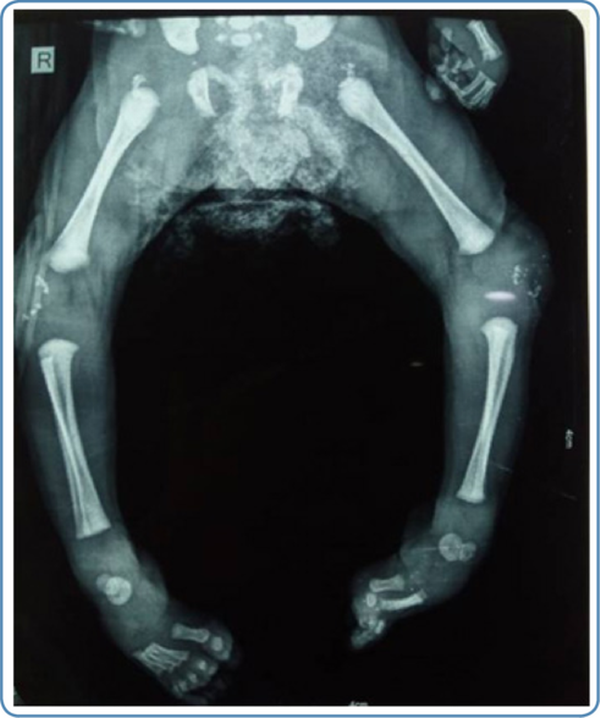

Chondrodysplasia punctata at the knee and/ or ankle joints and along the vertebrae in early childhood and rhizomelic shortening are noted in skeletal radiographs in cases with RCDP and Zellweger syndrome (Figure 6). In addition, vertebral cleftsare seen on the skeletal survey in RCDP.

Figure 6

Skeletal radiograph showing chondrodysplasia punctata at the knee joint in a child with rhizomelic chondrodysplasia punctata